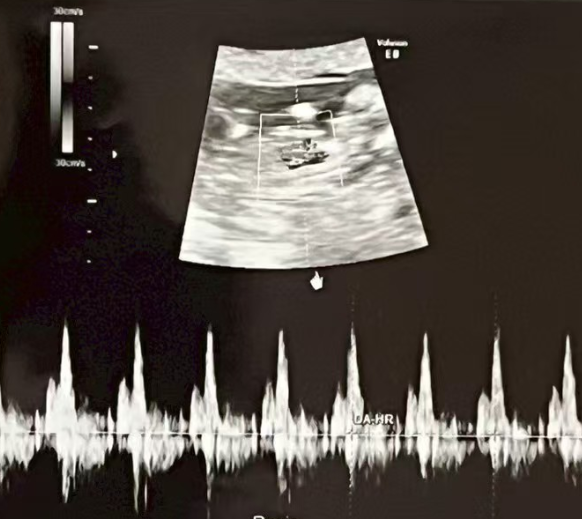

1月24日,孕7周,已成功看到胎心。

小小的心跳如期而至,生命的第一份回應悄然出現。